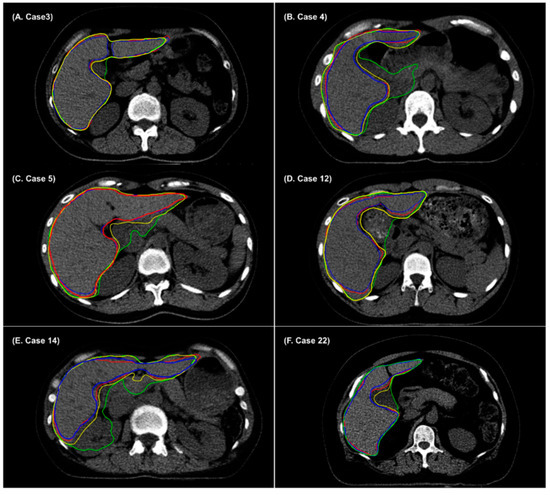

3. Results